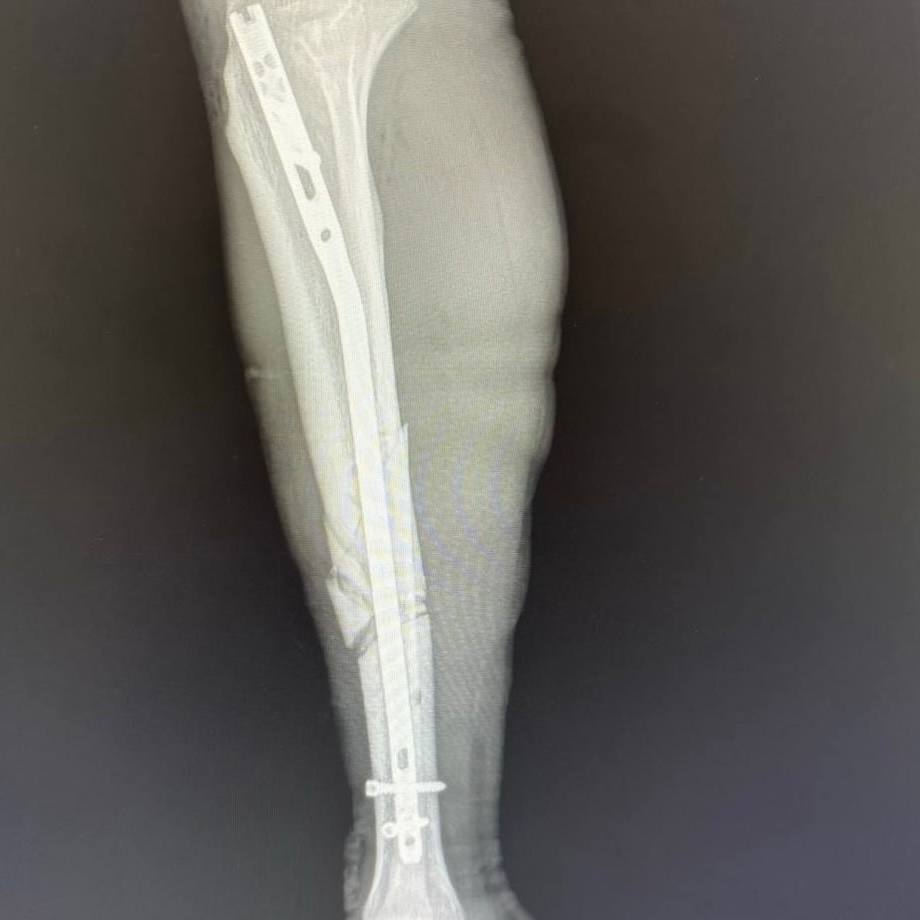

После обследования пациента экстренно прооперировали. Пациенту диагностировали множественные переломы костей лица, рёбер в нескольких местах, правой и левой плечевых костей, седалищной кости и правой голени. Правое лёгкое оказалось разорванным, в плевральной полости скопились воздух и кровь. В ходе операции пациента стабилизировали, установили аппараты внешней фиксации и перевели в реанимацию травмоцентра.

В течение месяца пациенту провели пять операций остеосинтеза. Хирурги поэтапно возвращали смещённые костные отломки в правильное анатомическое положение и фиксировали их.